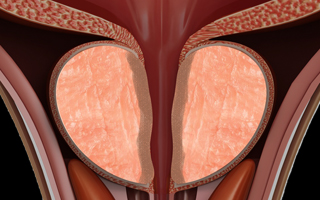

플라즈마 기화술의 시술방법

01

1단계

플라즈마 장치를 요도를 통해 삽입합니다.